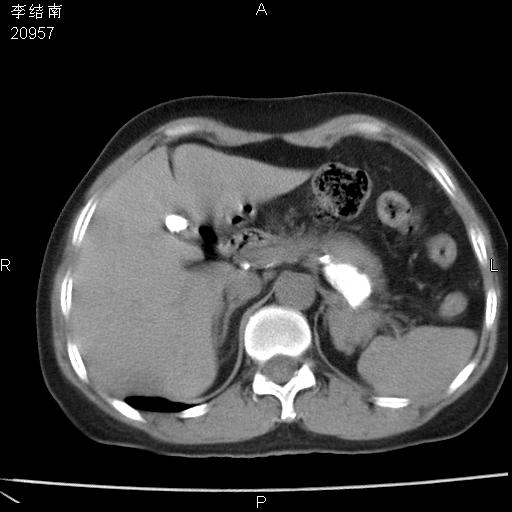

患者女,45岁,以右侧腰部包块来就诊,局部有压痛,皮肤颜色正常。因为是熟人扫的范围较大,患者有胆结石,胆源性胰腺炎病史。请大家看看,有手术病理。

可能大家觉得片子的质量不好,当时是做下腹部扫描,所以没有常规喝水,右腹壁的病灶当时是,密度不均有钙化影,局部骨质没见破坏,肝脏应该是受压的表现,所以当时考虑为腹壁的良性占位,各位老师考虑的神经源性肿瘤,我当时还真没想到,胰腺是胰腺炎治疗后改变.膈脚旁的混杂密度包快不好考虑什么,到上级医院做增强(腹部)+肺部平扫后,发现腹壁的病灶呈不均匀性强化局部可见囊性灶,当时考虑为腹壁结核,最具戏剧性的是膈脚旁的混杂密度灶确是胃的一部分,而腹壁的病灶确是脂肪瘤(简直不可思议)但是我亲眼所见在我们县医院开的.

很不好意思 ,患者后来手术切口裂开,临床医生作了病理证实是腹壁结核。

[病理诊断] CT13183腹壁结核!